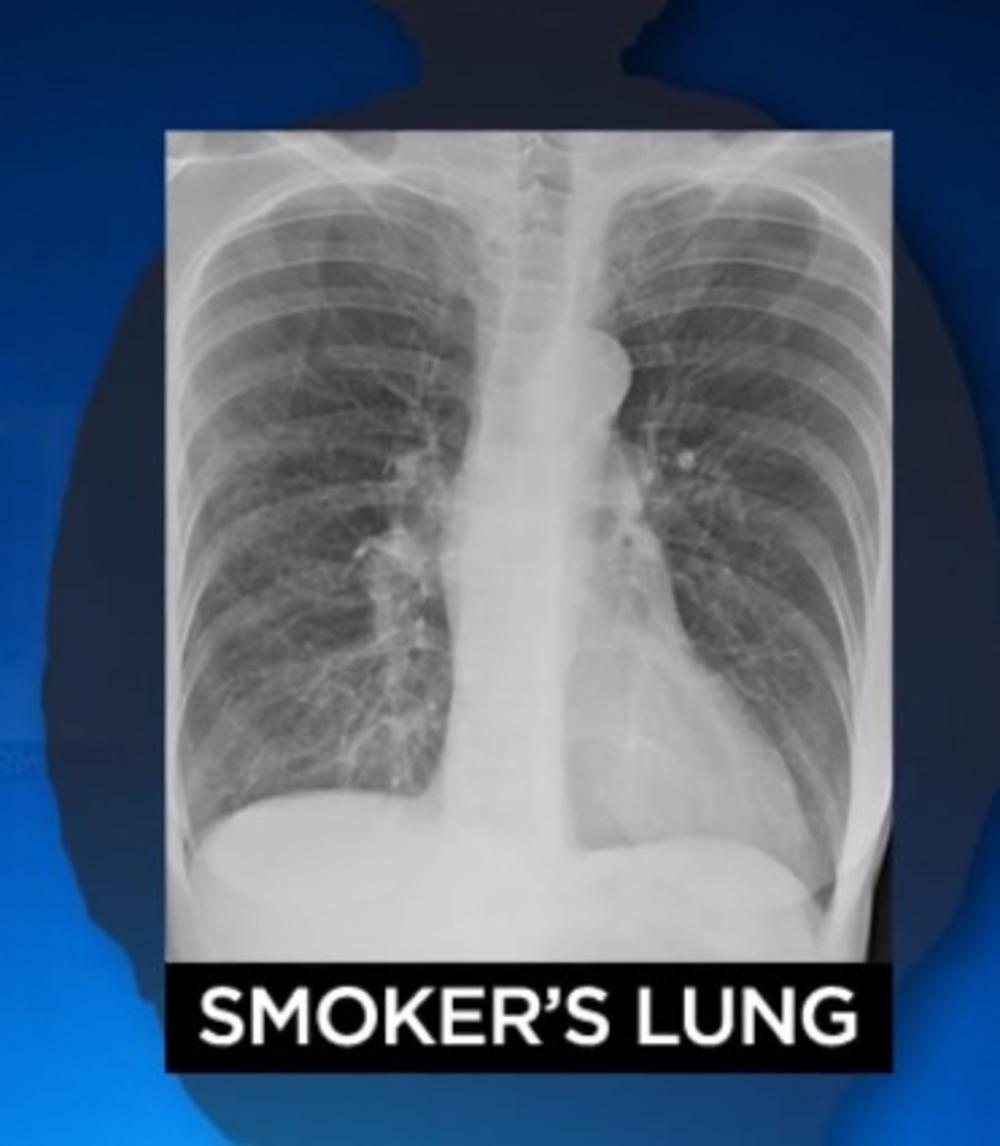

Легкие курильщика рентген

Легкие курильщика на флюорографии